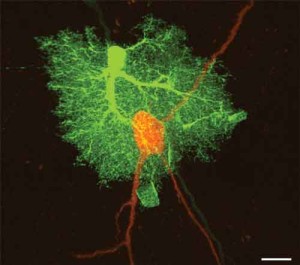

Nuove ricerche pubblicate sul ‘Journal of Neuroscience’ suggeriscono che modificando i segnali inviati dagli astrociti, cellule cerebrali a forma di stella, si puo’ contenere la diffusione dei danni dopo un ictus ischemico al cervello. astrocitiLo studio, condotto sui topi, e’ opera della Tufts University School of Medicine e ha determinato che gli astrociti giocano un ruolo critico nella diffusione del danno che segue l’ictus. L’ictus e’ causato da coaguli sanguigni che bloccano il regolare flusso di sangue (e quindi di ossigeno) nel cervello. Quando questo la circolazione viene ripristinata, i neurotrasmettitori continuano a compensare la mancanza di ossigeno, danneggiando le cellule del cervello anche dopo la fine dell’ictus. Il nuovo studio ha mostrato che gli astrociti, il cui numero supera di 10 a 1 quello degli altri neuroni, inviano segnali che promuovo questo tipo di danno cerebrale: modificando questi segnali e facendoli diminuire, e’ possibile limitare il danno, tramite la regolazione dell’attivita’ dei neurotrasmettitori che e sono responsabili.